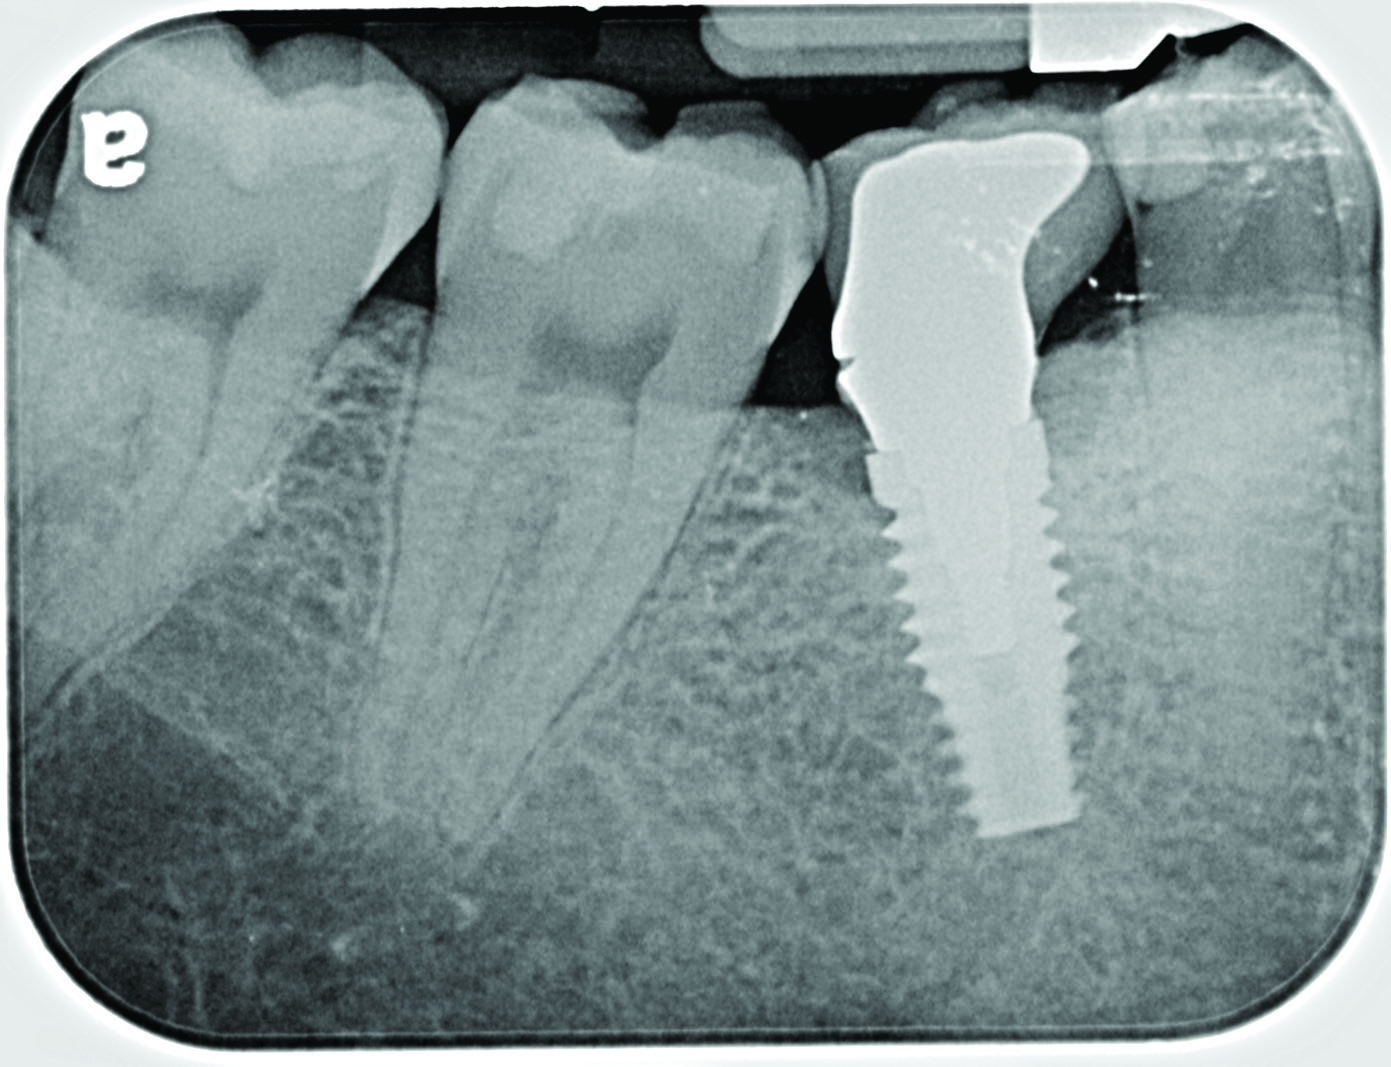

Fig 13. Radiograph depicting peri-implantitis.

Figure 13